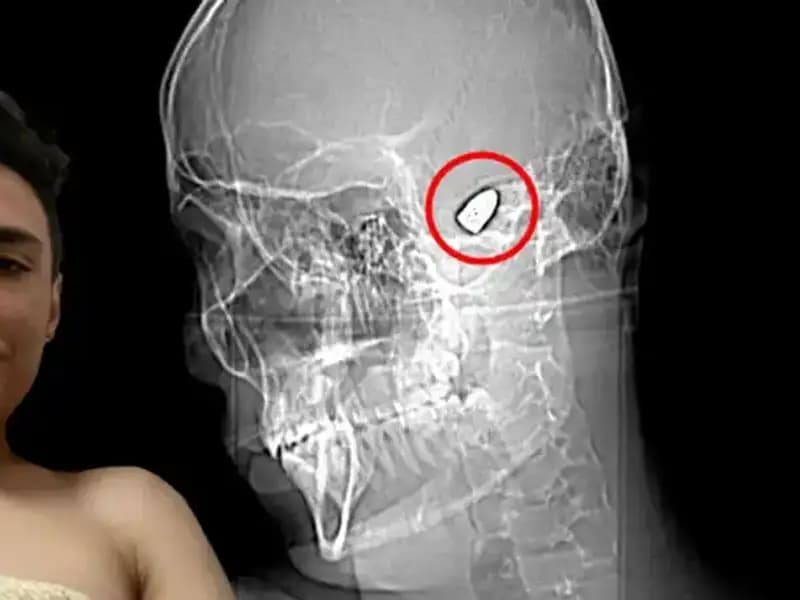

Kafasında Patlayıcıyla Gezen Adamın Hikayesi Duşunuzu AşacakBir adam, kafasında patlayıcıyla yaşam mücadelesi veriyor. Gerçek hikayesi cesaret ve direniş dolu.